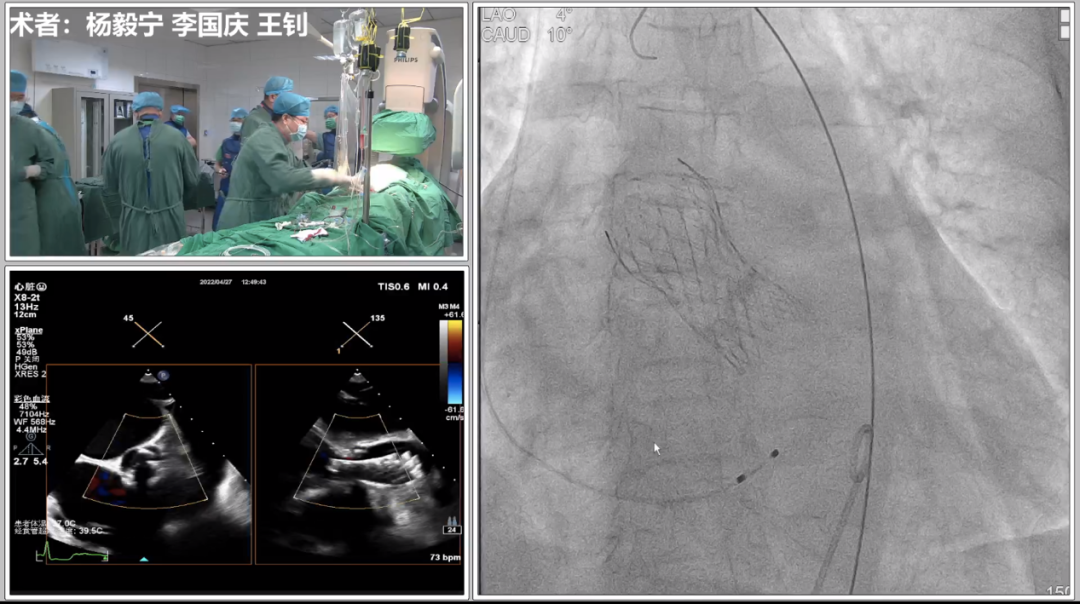

2022年4月27日,新疆维吾尔自治区人民医院杨毅宁教授团队成功为一名高危、重度主动脉瓣膜狭窄患者植入了美敦力Evolut PRO经导管主动脉瓣膜(TAVR),此例植入为新疆首例,同时也是全国首批。

该病例为70岁女性患者,间歇胸闷气短17年,反复住院药物保守治疗,效果不佳,10日前症状加重,伴有胸痛、头晕、黑朦,双下肢水肿,转于我院就诊。经检查分析,诊断为重度主动脉瓣狭窄,风心病,患者主动脉瓣叶增厚,左心耳血栓,左冠开口小于10mm,存在一定冠脉阻塞风险,右侧股动脉分叉在股骨头中点,左侧股动脉分叉高于股骨头中点,双侧髂外动脉最小直径小于5.5mm,主动脉弓角偏大,对血管介入造成难点,同时易引起血管并发症,手术难度大。经杨毅宁教授团队充分评估,对患者采取全麻下经食道超声监测,选用目前行业最低入路要求美敦力递送系统配合自带内联鞘进行介入。

根据术前CT分析,结合患者瓣膜钙化情况,决定预装Evolut PRO 26mm瓣膜,采用超声引导下穿刺,确保入路精准,对血管损伤最小。

首先进行球囊预扩、造影,判断左右冠开口情况,实际显示冠脉灌注良好,将根据瓣膜植入后情况再决定是否进行冠脉干预,由于患者血管入路短径小于5.5mm,使用大鞘将难以通过并造成血管损伤,采用内联鞘直接进入递送系统,超强的顺应性使得递送顺利过弓和跨瓣。

在CUSP OVERLAP投照角度下进行瓣膜释放,释放过程中杨毅宁教授密切关注患者各项体征指标以及各器材位置情况,稳步操作最终达到预计位置精准定位,术后跨瓣压差即刻降低至0,患者双侧冠脉灌注良好,无反流,超声检测血流动力学明显改善,手术取得圆满成功。 中心简介 新疆维吾尔自治区人民医院始建于1934年,是一所集医疗、教学、科研、预防、保健和社区卫生服务为一体的大型综合性“三级甲等医院”。曾先后荣获“全国文明单位”、“全国百佳医院”、“全国五·一劳动奖状”、“全国卫生系统先进集体”、“全国万名医师支援农村卫生工程先进集体”、“全国十大百姓放心医院”、“全国卫生系统思想政治工作先进集体”、“自治区民族团结进步模范单位”等荣誉称号,是中国医院竞争力·顶级医院100强。 专家简介 杨毅宁 新疆维吾尔自治区人民医院 医学博士,博士生导师,教授、主任医师。 现任新疆维吾尔自治区人民医院党委副书记、院长。2004年和2007年分别于新加坡国立大学医院导管室和德国Mainz Johannes Gutenberg大学临床医院心内科研修冠状动脉介入治疗。目前研究方向为冠心病、先天性心脏病及瓣膜病的介入治疗及相关基础研究。国务院特殊津贴专家,新疆自然科学专家。2017年入选“国家百千万人才工程”并被授予“有突出贡献中青年专家”荣誉称号,第十二届“中国医师奖”获得者,先后入选教育部新世纪优秀人才计划,自治区“天山雪松计划”科技创新领军人才后备,“天山英才”培养计划第一层次。 主持国家重点研发计划1项,国家自然科学基金6项,教育部新世纪优秀人才计划项目1项,自治区级科研项目14项,参与国家自然科学基金、国家“十一五”计划子课题及横向课题、自治区重大专项等20余项研究。以第一作者或通讯作者身份发表学术论文250余篇,其中SCI收录论文60篇,CSCD收录论文174篇。主参编专著16部,荣获自治区科技进步奖10项,其中一等奖4项、二等奖6项,荣获中华医学科技奖2项,2020年被评为自治区“最美科技工作者”。在临床工作中不断开拓创新,年均完成经皮冠状动脉介入治疗(PCI)2000余例,先心病介入封堵术350余例,积极开展和推广IVUS、OCT、远隔缺血适应治疗等新技术的临床应用。在疑难危重症治疗上,使用TAVR、ECMO等新技术,成功救治多名危重冠脉、先心病、瓣膜病患者。